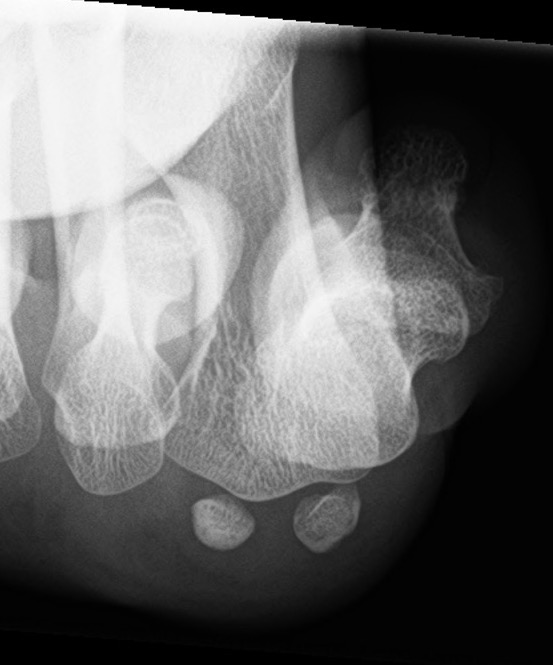

Imaging

Bilateral standing xray can help

Unclear if bipartite or stress fracture

Irregular borders suggest fracture rather than bipartite

CT demonstrates irregular borders consistent with fracture of tibial sesamoid